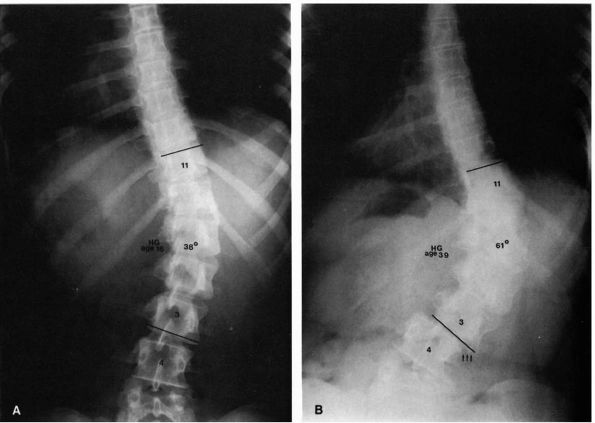

FIGURE 16-11. (A)

Sixteen-year-old girl with a 38° right lumbar curve from T11 to L3. Her skeletal maturity is assessed as grade 5 on the Risser scale. (B) At 39 years of age, her right lumbar curve has increased to 61°. Note the translatory shift of L3 on L4 (arrows). (Weinstein SL. The natural history of scoliosis in the skeletally mature patient. In: Dickson JH, ed. Spinal deformities, vol 1. Philadelphia: Hanley & Belfus, 1987:199) |